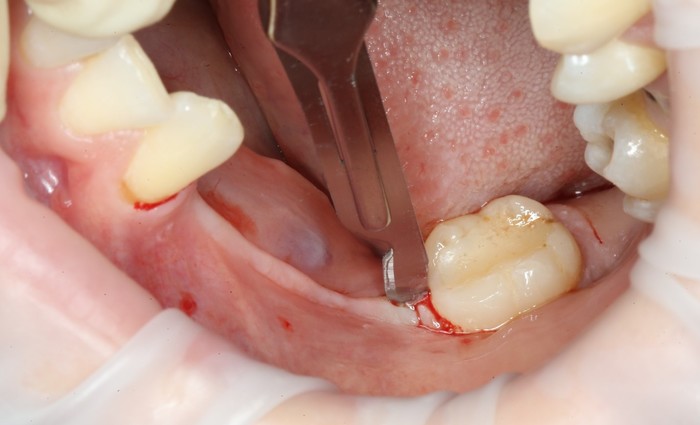

В связи с тем, что Руслан приезжает из другого города, первым делом я провел удаление всех зубов, которые невозможно было сохранить. Потому как часики тикают, а заживление после удаления занимает около 2 - 3 месяцев.

Уже на следующий день была запланирована имплантация.

На верхней челюсти было дополнительно удалено два боковых резца с одномоментной установкой имплантатов, так же они были установлены в области четверок и шестых зубов. Дополнительно было проведено наращивание костной ткани - двусторонний синус - лифтинг. О том, что это такое, можно почитать ТУТ и ТУТ.